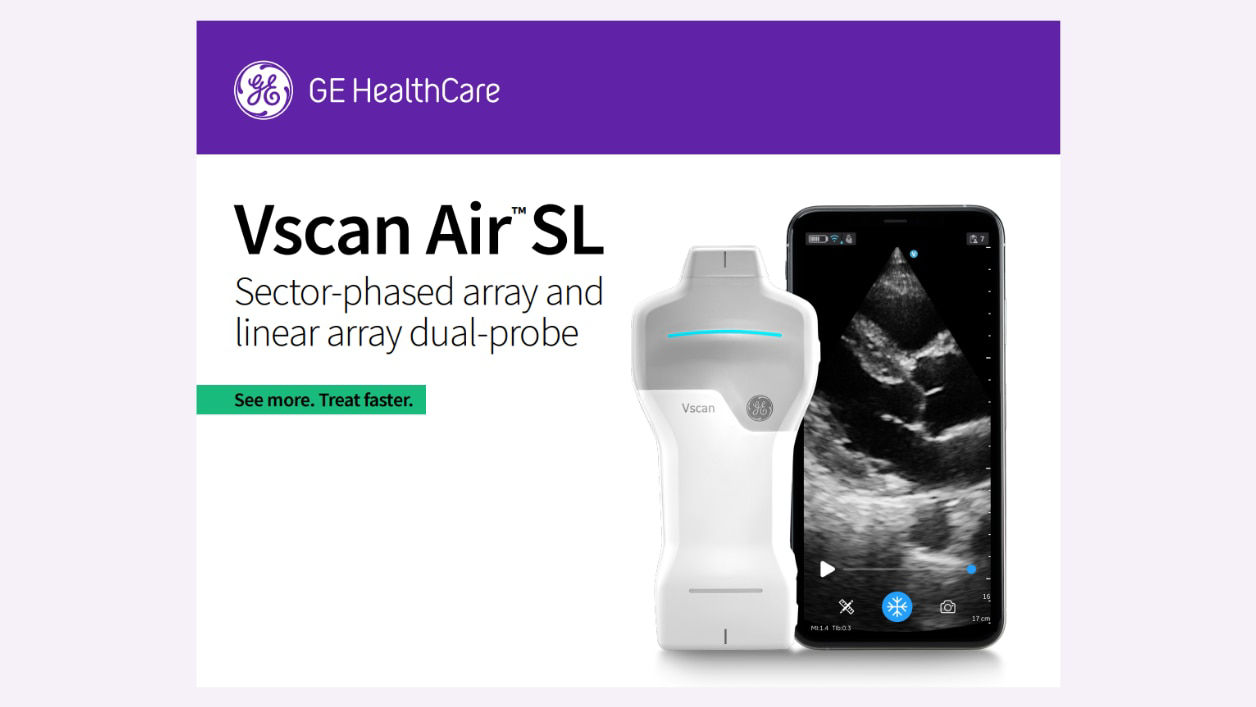

Vscan Air provides a cost effective ultrasound solution for your primary care practice.

Available AI features assist in clinical image interpretation and can help enhance diagnostic accuracy.

Vscan Air enables early detection of various conditions, allowing for timely interventions and improved prognosis.

Seamless pairing with a mobile device and intuitive to navigate.